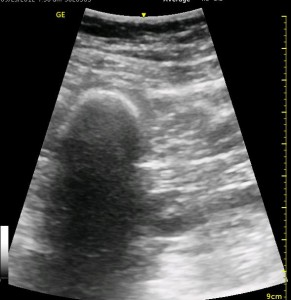

The following ultrasound image shows typical relationships of the sonoanatomy of the anterior sciatic nerve block. The femur is at 4cm on the right (lateral) of the image seen as a bright white horizontal line. Typically, there is a bone shadow below it, though there is some artifact below the femur here. The femoral vessels are seen between the 2cm and 3cm marks just to the right of center as a darkened area. They really can be determined by pausing for the appearance of arterial pulsation and venous compressibility. The adductors are seen to the left of the femur as a darkened area. Just deep to this between the 6cm and 7cm mark is a brightened rectangular shape, the sciatic nerve. The brightness fill fade with rocking of the probe over it. The nerve can be approached from the medial or lateral aspect of the probe, and moving the probe medially will sometimes allow for a better trajectory.

The image above is not an obvious one, and I did that on purpose. You have to get used to the idea that you will not always have a ‘super distinct’ image with this approach, and you will often need to use a number of additional clues to find your target and then to put local around it. I think the only way to really get a handle on being able to identify the basic elements is to look at several images over and over, so I have provided several below for you to use for practice. Note that the sciatic nerve will ‘poke out’ from behind the femur to different degrees depending on your orientation to the femur as well as to how far up or down the femur you go. It will be seen more if you are proximal. See how well you can identify the structures in the images below.